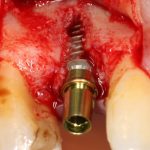

Рекомендации по установке имплантов. Для всех. Часть V.